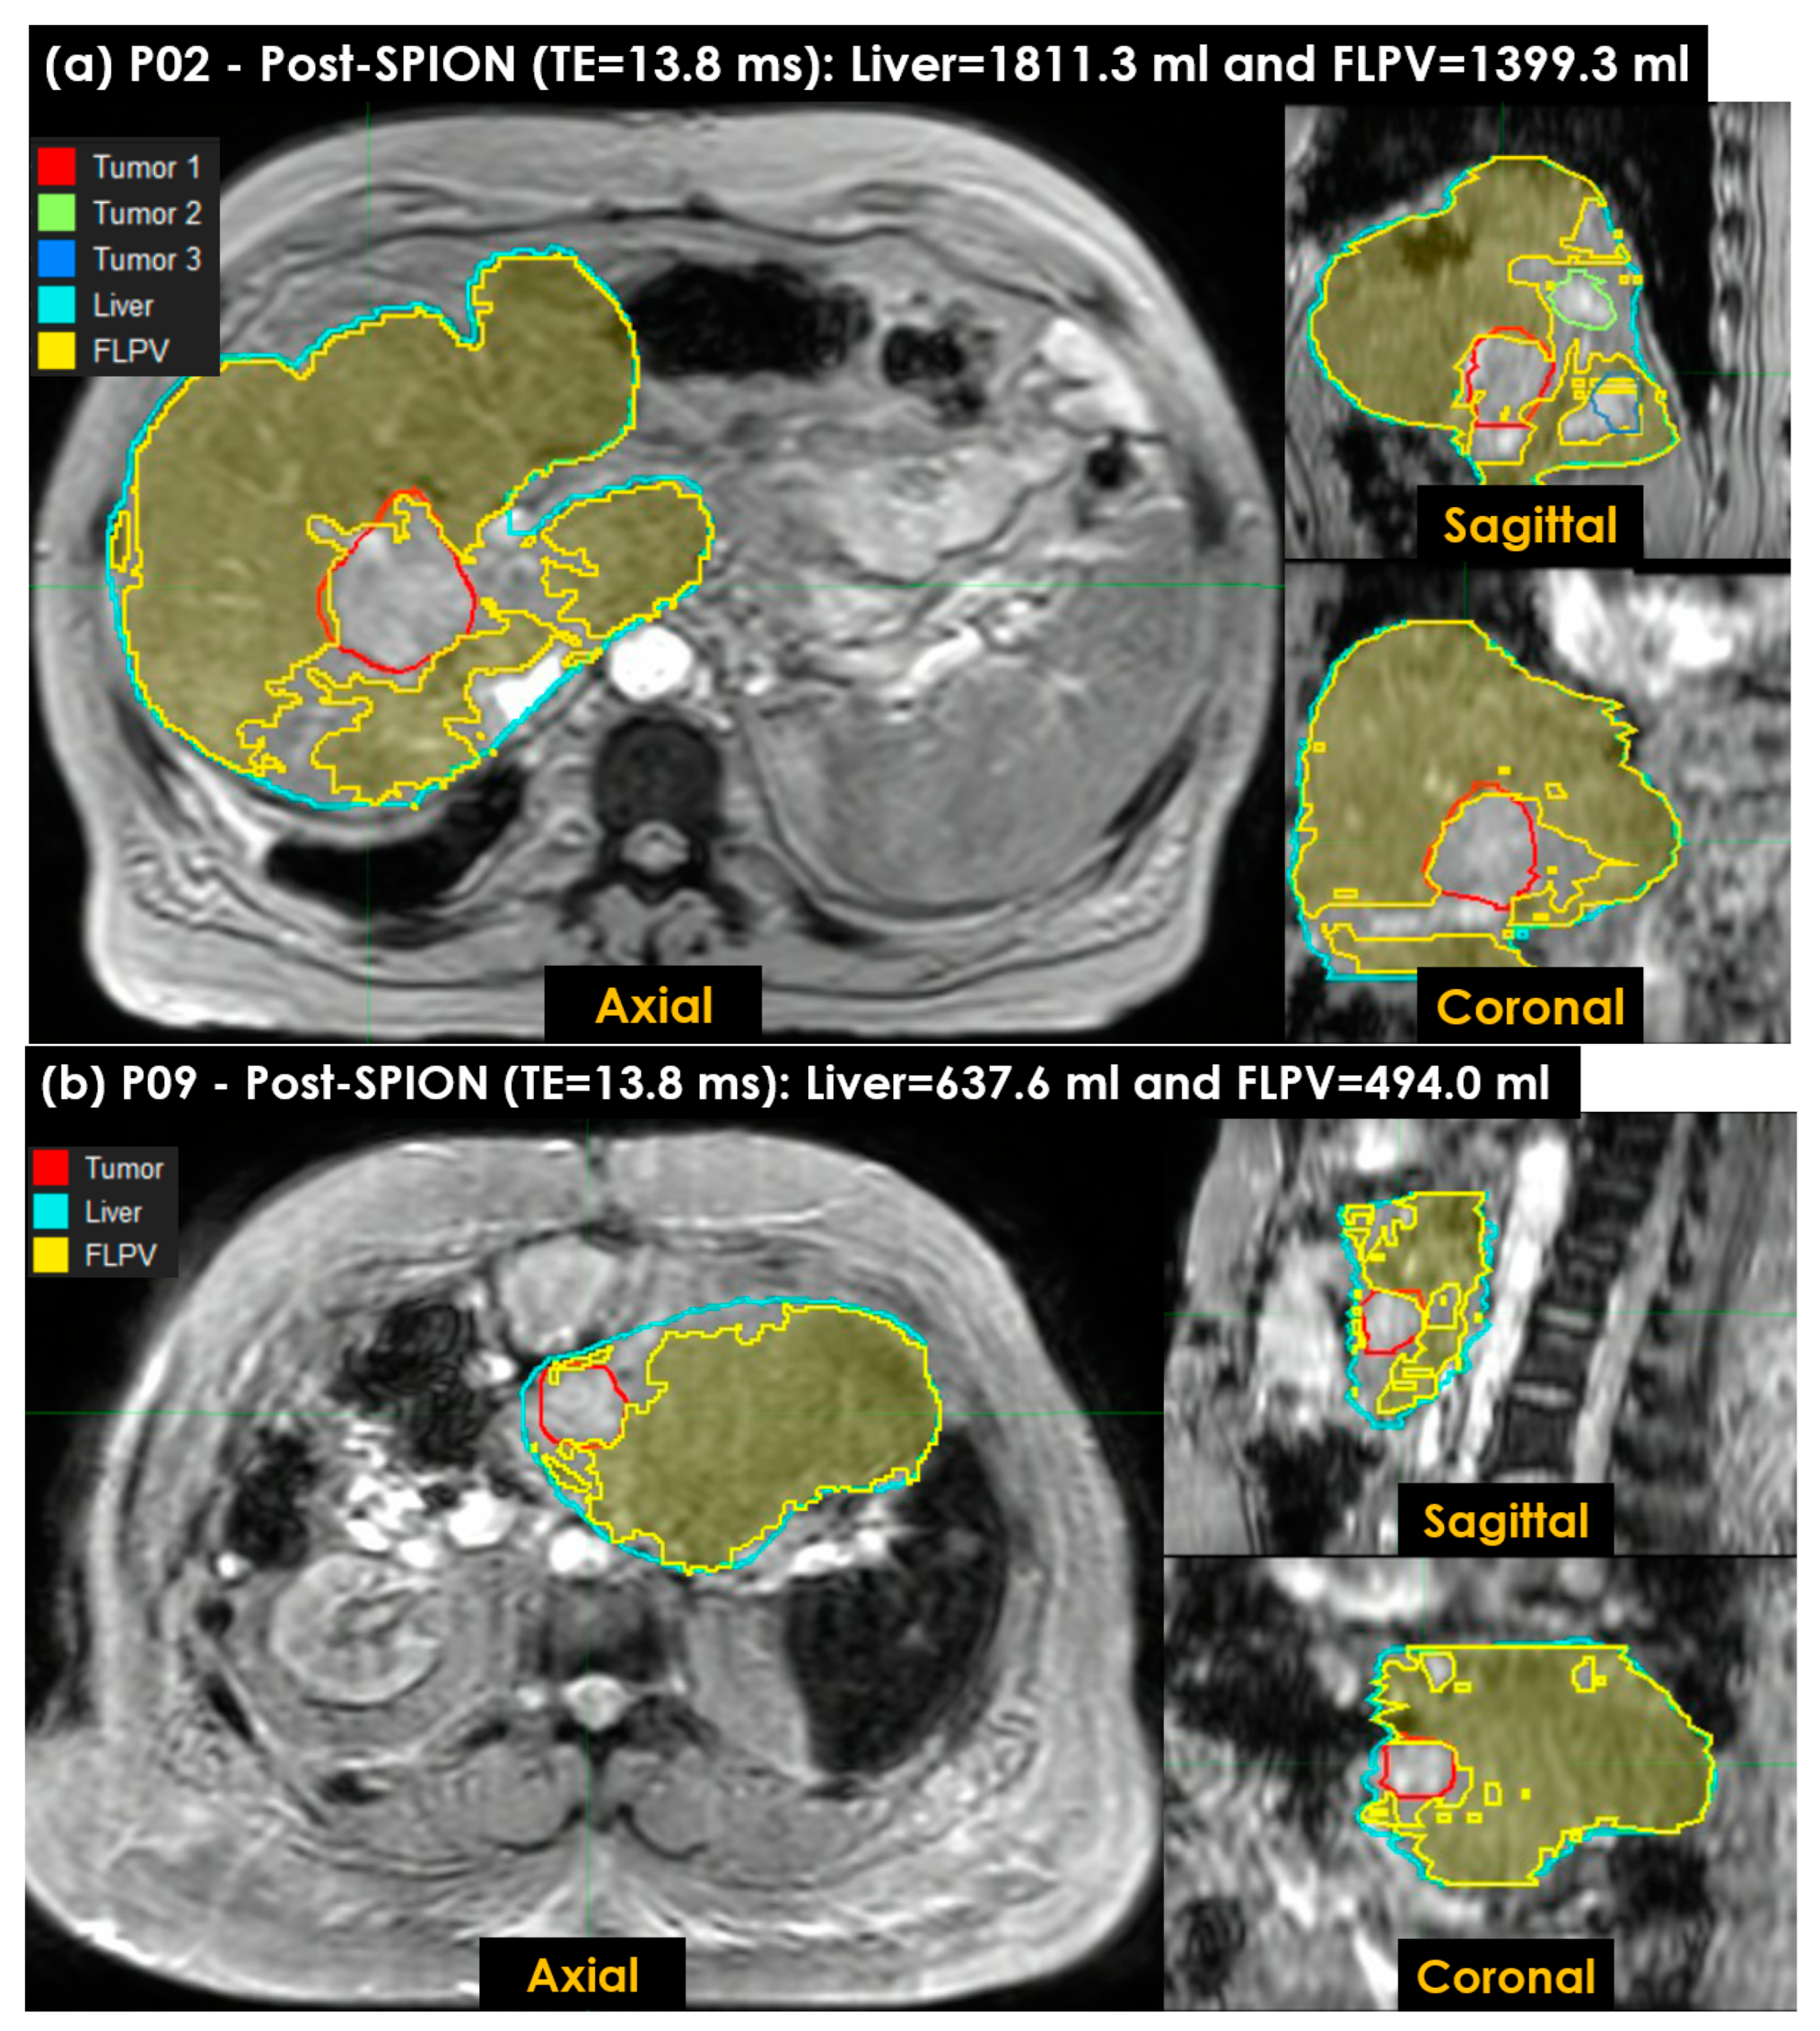

Figure 7 shows the FLPV identified in the auto-contouring tool with the THRES-MEANR2* of the PRE-POSTR2* approach. The FLPV was clearly identified with minimal overlapping for three tumors in patient P02 (Figure 7a) and a tumor in P09 (Figure 7b). The FLPVs in patients P02 and P09 were 1186.0 mL (65.5%) out of 1811.3 mL and 357.6 mL (56.1%) out of 637.6 mL, respectively. P02 had three tumors, contoured in red, (Tumor 1), green, (Tumor 2) and blue, (Tumor 3). P09 had a single tumor, contoured in red. All tumor illustrations demonstrate the efficiency of auto-contouring the FLPV on axial, sagittal and coronal 3D planes.

Figure 7. The functional liver parenchyma volume(s) FLPV(s), identified using the THRES-MEANR2* of the first PRE-POSTR2* approach in an auto-contouring in-house tool, were overlaid on liver images. (a) Three tumors in patient P02, contoured in red (first tumor), green (second tumor) and blue (third tumor), are illustrated to demonstrate the efficiency of the in-house tool for identifying the FLPV; (b) a single tumor in patient P09, contoured in red, is also illustrated. Both FLPVs of P02 and P09 are clearly distinguished from all tumors with minimal overlapping between the FLPV and non-FLPV (tumor, hepatic vessels, liver fibrosis and scarring associated with hepatic cirrhosis).